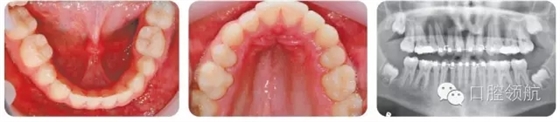

圖3.15中使用玻璃離子粘結(jié)的矯治器有什么作用?

這是一個改良的橫腭桿,其作用是在去除主動擴(kuò)弓裝置后,維持上頜牙弓的擴(kuò)寬效果。在上頜弓絲更換到不銹鋼方絲時,可以去除該橫腭桿。其改良之處是增加了一個從第一磨牙伸向第二前磨牙的鋼絲,從而同時維持前磨牙區(qū)的擴(kuò)弓效果。

為什么該病例選擇拔除下頜第二前磨牙?

● 解除擁擠。

● 縮窄下牙弓橫向?qū)挾取?p style="text-indent: 2em; text-align: left;">● 維持前牙覆不減少。

圖3.16展示了患者治療結(jié)束時的口內(nèi)像和面像,其糾正后牙反的療效穩(wěn)定嗎?

擴(kuò)弓治療存在不穩(wěn)定性。長期的隨訪調(diào)查顯示,擴(kuò)弓治療結(jié)束后,不論是牙弓或者牙槽骨都存在顯著的縮窄。因此,擴(kuò)弓治療結(jié)束后需要長期保持,這里推薦使用Hawley式保持器。與此同時,拔除下頜第二前磨牙以及下牙弓的縮窄相對而言更加穩(wěn)定,因此有助于反糾正療效穩(wěn)定性的提高。